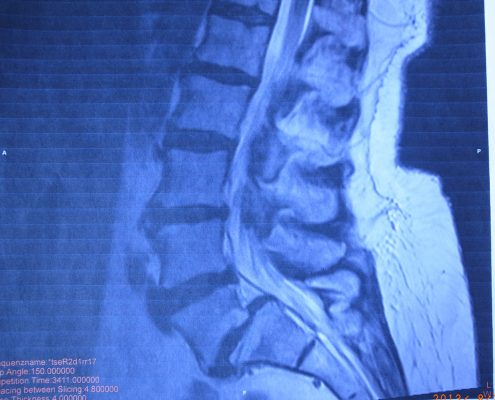

Auf diesem Video ist eine meiner Patientinen zu sehen die vor der ersten Dotai-Therapie nur mit fremder Hilfe und am Treppengeländer hochziehend die Treppe in meine Praxis hinauf kam. Doch schon nach der ersten Behandlung konnte sie wieder eigenständig, ohne jede Hilfe und freihändig die Treppe rauf- und runterlaufen!